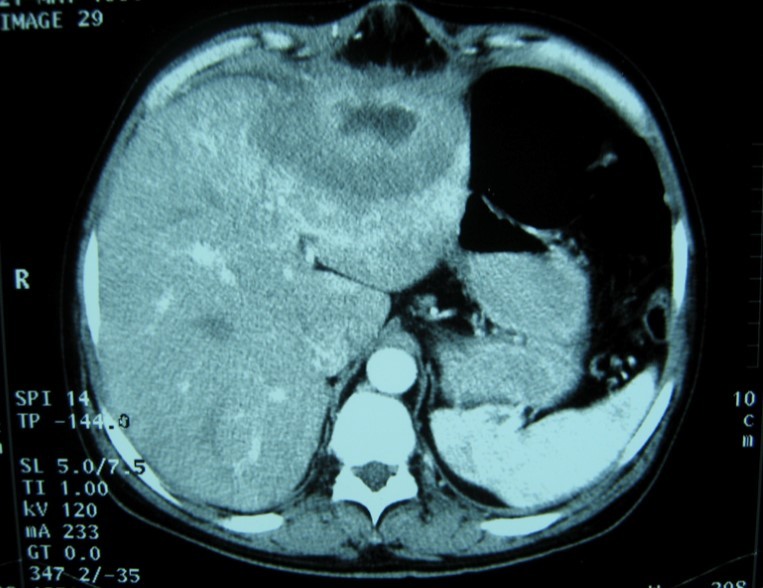

Laboratory analysis showed hemoglobin, 10.9 g/dL; white blood cell count, 9,800 cells/mm3, serum albumin, serum total bilirubin, alanine aminotransferase, aspartate aminotransferase, prothrombin time, hepatitis B surface antigen, and antibodies to hepatitis C, serum alpha-fetoprotein (AFP), carcinoembryonic antigen and carbohydrate antigen 19-9 (CA 19-9) were within normal range. Blood cultures were negative. Chest x-ray was normal. Ultrasound of abdomen showed a 10 cm hypoechogenic lesion in left liver (Figure 1). An abdominal CT showed a well-defined heterogeneous mass situated in his left hepatic lobe measuring 10 cm × 7 cm (Figure 2, Figure 3). The lesion featured central necrosis, a hyper-dense rim and a mild enrichment from the arterial phase in the CT, The diagnosis of primary hepatic tumor was suspected. An ultrasonography-guided needle biopsy of the liver was scheduled in order to rule out malignancy and to have a complete diagnosis. Cytology demonstrated a tuberculosis granuloma, acid-fast bacilli culture was positive (Figure 4). Anti-tuberculous therapy including isoniazid, rifampin, ethambutol, and pyrazinamide were prescribed. The patient completed the 6-month course of medication with success. The patient’s appetite and body weight were restored to previous levels. One year after the completion of treatment, the patient remained completely asymptomatic with disease free.

Figure 2.Abdominal computed tomography with intravenous contrast showing 10x7 cm low-density focal lesion

Figure 3.Abdominal computed tomography with intravenous contrast showing the lesion with ring enhancement.

Computed tomography (CT) and magnetic resonance imaging (MRI) are helpful in diagnosis.

CT findings of tuberculosis abscesses can show low-density focal lesions with or without ring enhancement on contrast administration. These have also been seen in necrotic tumor such as hepatocellular, inflammatory disease and metastatic carcinoma 12.